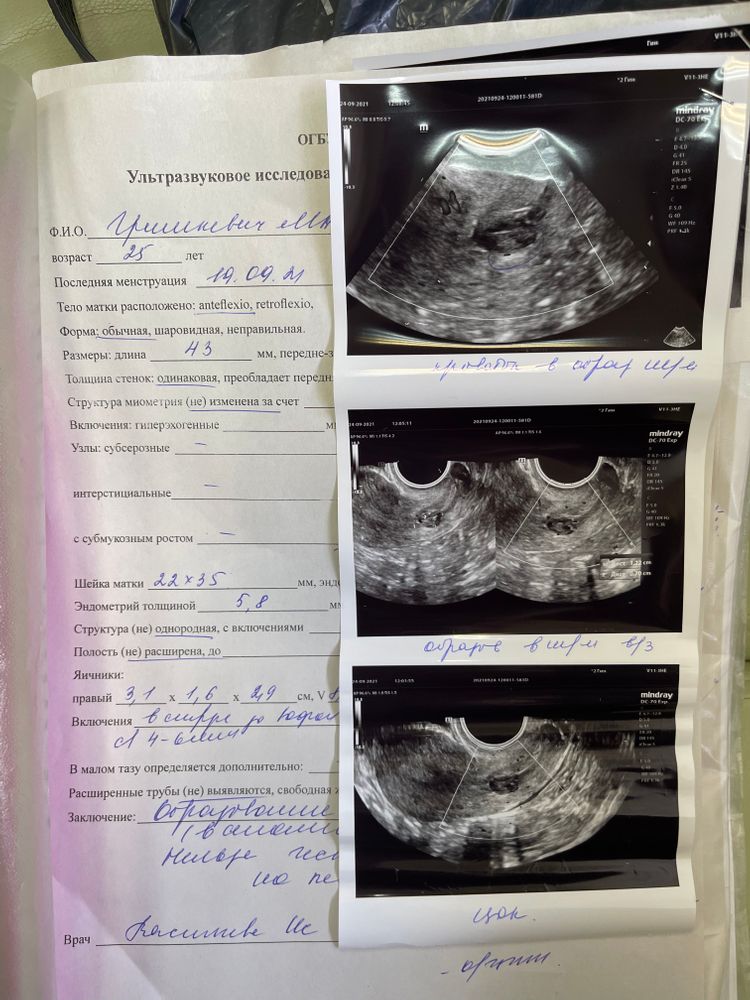

СтимуляцияСходила на узи образование в цк шм так и есть 11 мм, онкоцитология пришла хорошая.

никто не может понять что это и мешает ли оно зачатию. Ре говорит нет, узист говорит да 🤯🤯🤯